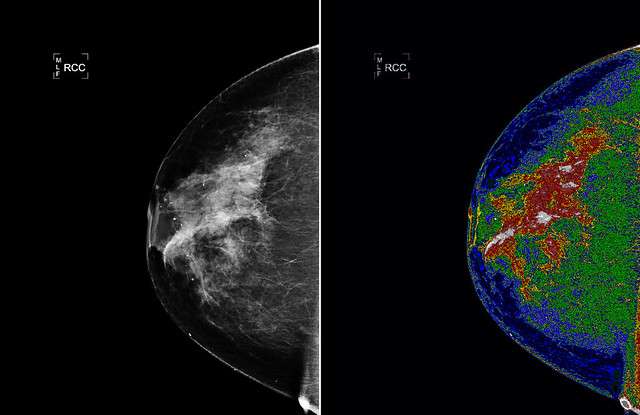

The field of medicine is continually changing to meet the current needs of people around the world. Although many diseases such as cancer seem to be on the rise, early detection now helps to save the lives of many patients. Thanks to modern medicine and new advancements in bioimaging using light technology, at-risk patients are being identified even earlier so that necessary measures may be taken to ensure proper treatment is provided.

Modern medicine utilizes technology for more accurate and precise evaluation of internal body imaging. Light technology has been adapted as a safe and non-invasive method for bioimaging that provides an in-depth view of soft human body tissues.

Image Source: Flickr user NEC Corporation of America